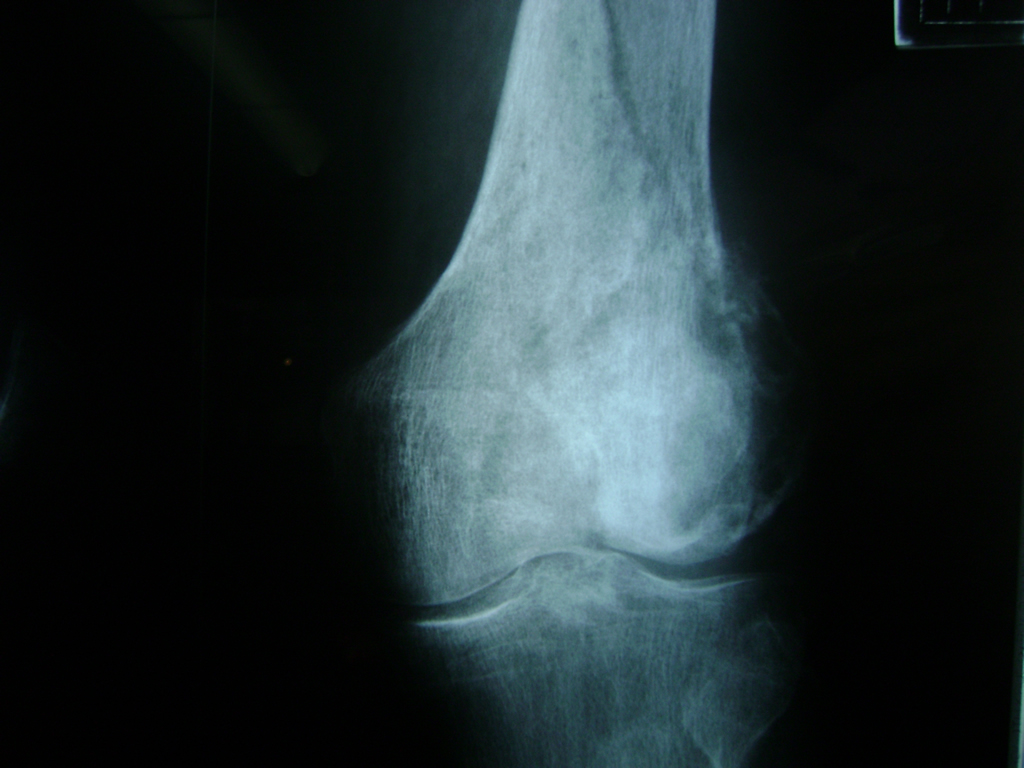

Cirugías de Rodillas